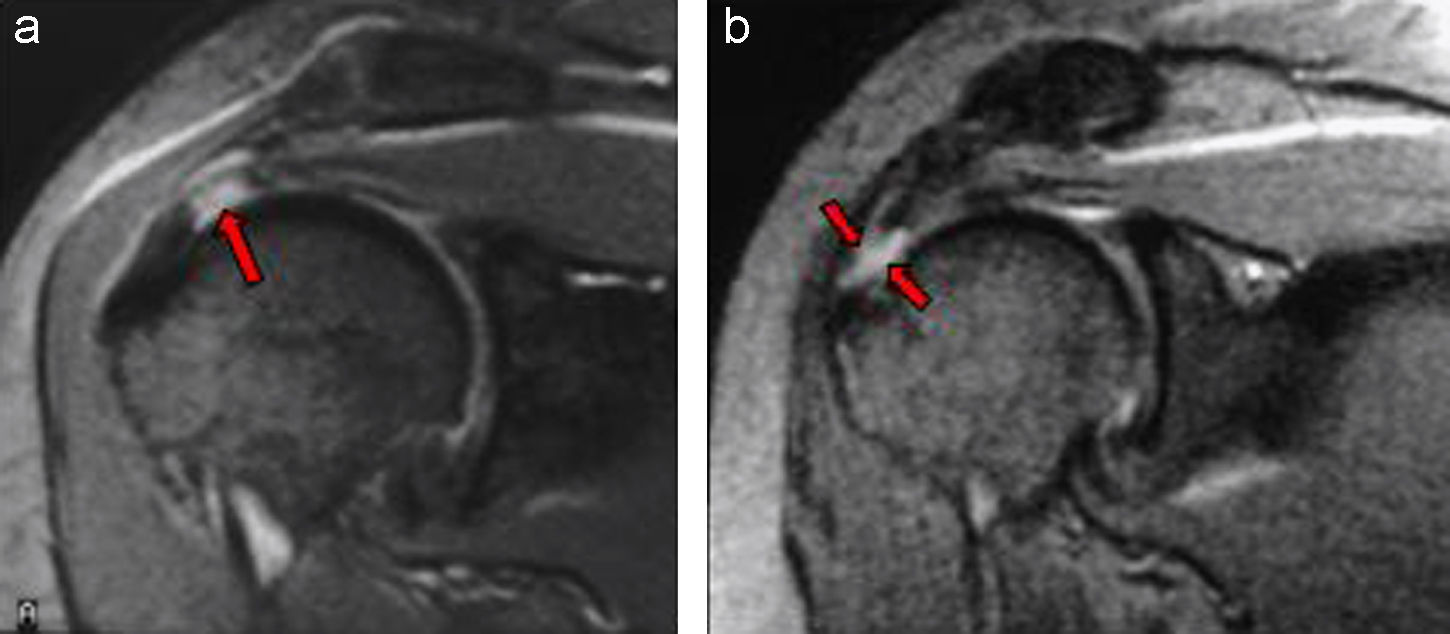

Hallazgos incidentales en resonancia magnética

26 noviembre 2018

Se revisa la frecuencia y la gravedad de los hallazgos inesperados en resonancias de cerebro, tórax y abdomen. British Medical Journal, 22 de noviembre de 2018